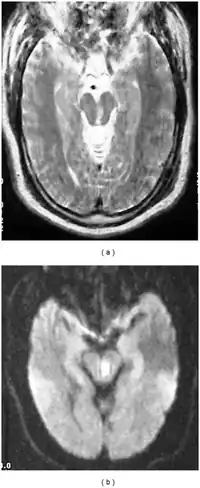

| a,b) Severely motion degraded axial T2-weighted and DWI images of midbrain demonstrate a subacute infarct within the left midbrain tegmentum | |

Claude's syndrome is a form of brainstem stroke syndrome characterized by the presence of an ipsilateral oculomotor nerve palsy, contralateral hemiparesis, contralateral ataxia, and contralateral hemiplegia of the lower face, tongue, and shoulder. Claude's syndrome affects oculomotor nerve, red nucleus and brachium conjunctivum.[1] Claude's syndrome is caused by midbrain infarction as a result of occlusion of a branch of the posterior cerebral artery.[2] This lesion is usually a unilateral infarction of the red nucleus and cerebellar peduncle, affecting several structures in the midbrain including: